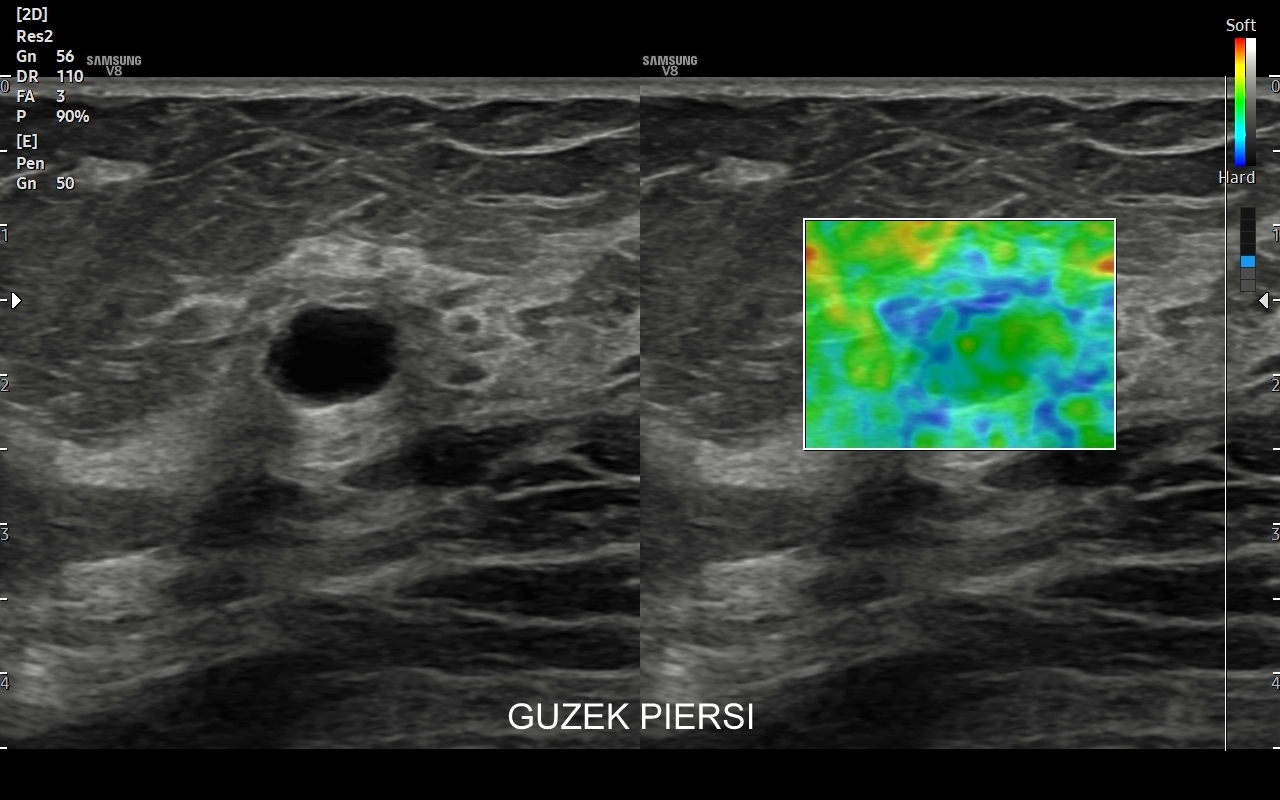

Badanie USG piersi jest podstawową i jedną z najważniejszych metod obrazowania gruczołu piersiowego. Wskazania do jego wykonania obejmują profilaktykę raka gruczołu piersiowego u kobiet oraz wskazania diagnostyczne. Profilaktyczne badanie USG piersi u kobiet wykonywane powinno być regularne raz w roku już nawet od 25 roku życia, w szczególności w przypadku rodzinnego obciążenia onkologicznego. Ze wskazań diagnostycznych badanie USG gruczołu piersiowego przeprowadzane jest w wypadku pojawienia się macalnego guzka piersi, deformacji piersi, jej stwardnienia i bolesności, stanu zapalnego, wycieku z brodawki sutkowej, czy powiększenia się pachowego węzła chłonnego. USG gruczołu sutkowego bywa również uzupełnieniem badania mamograficznego.

Badanie USG piersi z kontrastem (CEUS) jest najnowszą metodą diagnostyczną piersi i rozwinięciem badania multiparametrycznego USG (MPUS). Główną rolą badania CEUS piersi jest zwiększenie precyzji oceny guzków piersi pod kątem kwalifikacji w skali BIRADS, a przez to uniknięcie niepotrzebnych biopsji piersi. W przeciwieństwie do innych metod diagnostycznych zasadniczą zaletą badania CEUS jest możliwość jednoznacznego wykazania lub wykluczenia unaczynienia guzka piersi. Podejrzany guzek, którego unaczynienia lub cech nie można jednoznacznie ocenić w standardowym badaniu USG można poddać badaniu USG z kontrastem. Otóż w przypadku, gdy zmiana nie posiada unaczynienia to nie jest ona nowotworem. Niezależnie od kwalifikacji guzków łagodnych badanie CEUS ma możliwość w wielu wypadkach uwidocznienia ukrytych dodatkowych cech świadczących o złośliwości guzka.